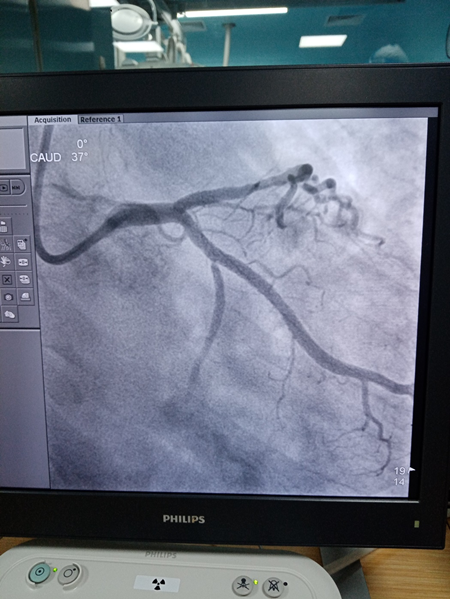

17时30分,患者到达医院,迅速按照预定路线快速送入介入手术室。消毒、铺巾、穿刺、造影。“回旋支堵了!”“来,上EBU导管”“上三件套”“上导丝”,高教授的话音落下,手术室内就显的有些安静了,能清晰听见的声音只有大家忙碌的脚步声和压力泵撤回的“啪啪”声,“导丝过去了,来球囊扩一下……”“好,小范造个影!”“好粗的回旋支啊,上支架!”“上后扩球囊”。在场的所有人员都为患者捏了一把汗。

18时05分,随着压力泵最后“啪”的一声,支架完美的贴靠在了回旋支闭塞的血管病变处,造影剂“划出了”一道靓丽的“风景线”!患者胸闷,胸痛症状明显缓解,生命体征恢复稳定。在场的团队成员舒缓了紧张的心情,患者得救了!